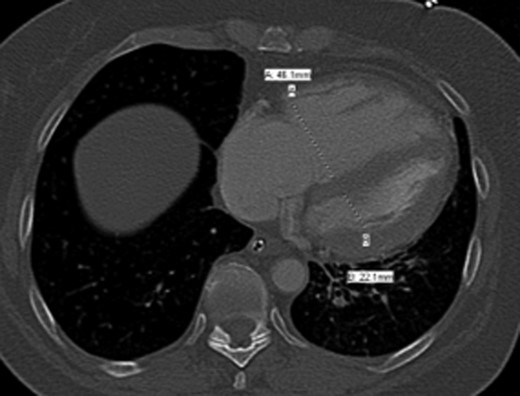

Once stable, imaging confirmed PE (Fig. 2) with a RV to left ventricle (LV) ratio of 2.1 (Fig. 3). The patient was then admitted to the ICU requiring inotropic support. Approximately 4 h later, the patient had concerning features of abdominal compartmental syndrome with increase abdominal distention and bladder pressures >25 mmHg was noted. Repeat imaging showed large volume hemoperitoneum emanating from the left hepatic lobe (Fig. 4). The patient underwent a decompressive laparotomy with a non-anatomic liver resection of segments I and II and temporary abdominal closure. Due to concerns of distal limb ischemia of the arterial cannulation site, an 8-Fr reperfusion cannula was placed in the left superficial femoral artery (SFA).

CTA chest showing significant pulmonary embolic clot burden occluding the right and left upper lung lobes.